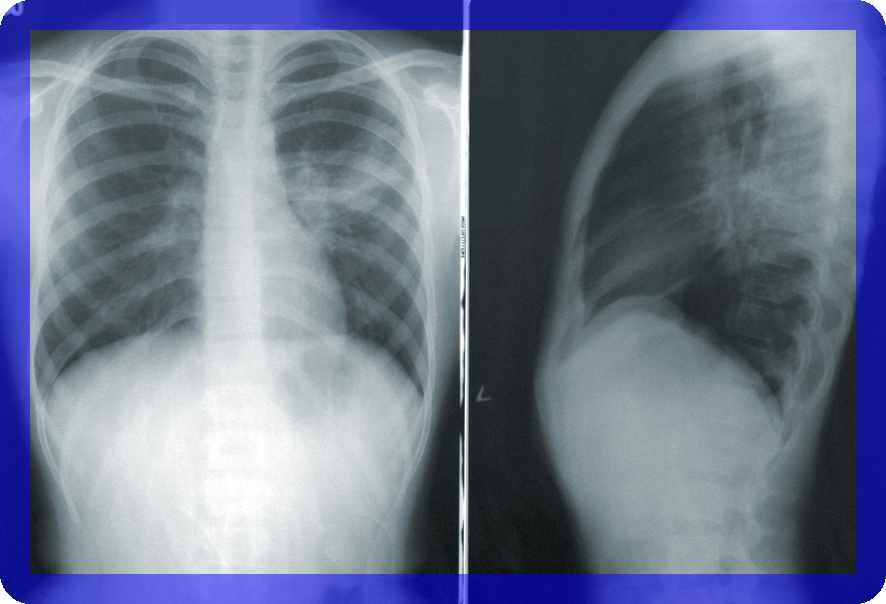

1. 흉부 엑스레이

흉부 엑스레이는 폐선암 초기 발견을 위한 기본적인 방법입니다. 빠르고 간편하게 폐와 심장의 상태를 확인할 수 있습니다.